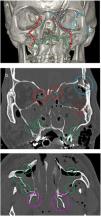

These are caused by a direct trauma to the malar process and are known as tetrapod fractures as they can involve four pillars delimited by sutures: frontozygomatic, zygomaticomaxillary, temprozygomatic and sphenozygomatic (Fig. 7).

(A) 3D representative of the pillars of the zygomaticomaxillary complex (ZMC) delimited by the frontozygomatic (purple), temporozygomatic (red), zygomaticomaxillary (green) and sphenozygomatic (yellow) sutures. (B and C) Axial and coronal computed tomography (CT) with a bone window. Zingg type B fracture of the ZMC; the zygomatic bone is free and displaced medially, reducing the orbital volume. (D–F) 3D reconstruction, axial and coronal CT with a bone window. Zingg type C ZMC fracture with involvement of the four pillars and comminution of the zygomatic bone.

With a view to surgical treatment, the Zingg classification divides them into three types31:

After a fracture, the forces of rotation applied to the zygomatic bone by the masseter muscle can lead to difficulty chewing or an increase in orbital volume and enophthalmos. If there is medial rotation of the free zygomatic fragment, the degree of defect to the floor of the orbit may be underestimated in comparison to surgical findings.

Particular attention should be given to the sphenozygomatic suture, as displacement, overriding or angulation of this suture is the most sensitive indicator of misalignment and changes in the orbital volume and implies a high likelihood that the orbital apex will be involved, compromising the optic nerve and ophthalmic artery. Moreover, these fractures are difficult to correct once the bone has set poorly.32–35